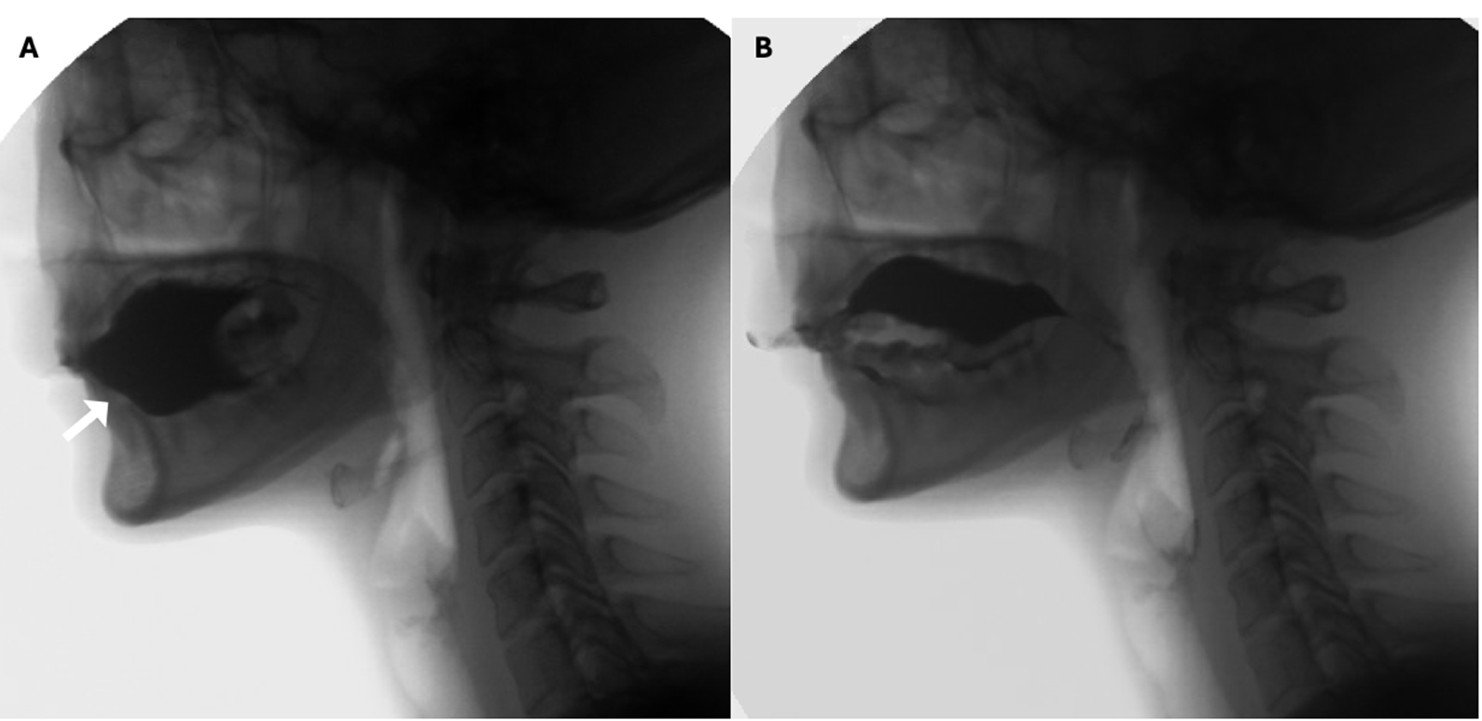

However, 5% of individuals may physiologically store boluses on the floor of their mouth instead of on the top of their tongues, a normal variant known as the dipping pattern of bolus hold. Unlike the more common tipping pattern, “dippers” use their tongue in a spoon-like motion to collect boluses from the floor of the mouth when transferring them to the pharynx. (Fig. 5) 25,26

Figure 5: Dipping pattern of bolus hold. Notice that before swallowing the contrast rests on the floor of the mouth (white arrow in A). In the oral propulsive phase, the tongue shows a spoon-like movement that scoops the entirety of the bolus (B)